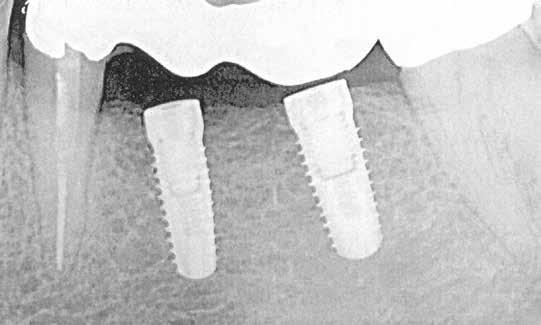

1–2. képek: Kiindulási helyzet.

3. kép: Új teleszkópos fogpótlás az 16, 15, 13, 23 és 27 fogakra.

Kiindulási helyzet

A páciens látlelete a következő:

• krónikus általános parodontitis

• a 24-től terjedő parodontális fekély

• hatástalan kapcsos felső fogpótlás (1-2. képek)

• új, teleszkóp-elhorgonyzású felső fogpótlás az 16, 15, 13, 23 és 27 fogak felhasználásával (3. kép)